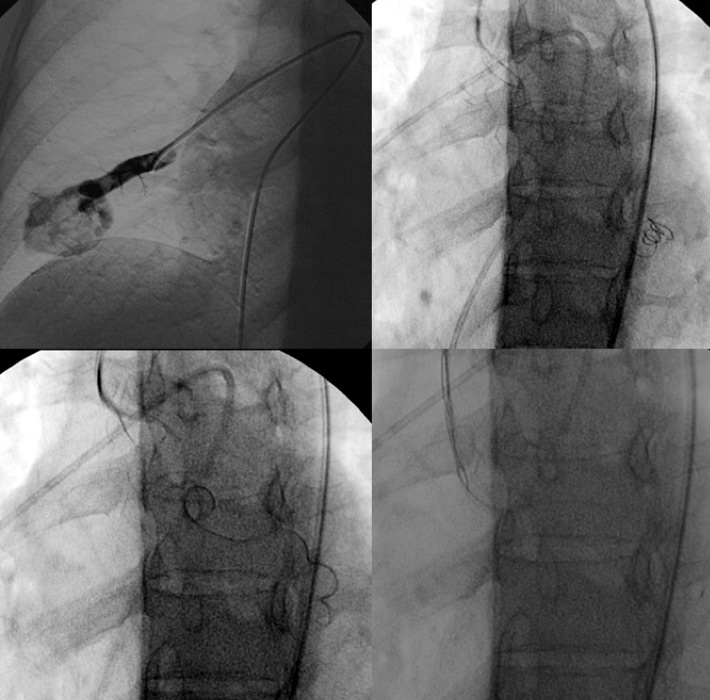

Figure 4

Embolisation attempt of a large pulmonary arteriovenous malformation (PAVM) with a feeding artery of 12 mm diameter with a 10/5 mm 10.035 Tornado® coil. Owing to the size of the AVM, distal translocation of the coil in the left ventricle occurred. A snare-assisted removal was then performed before a second and successful attempt at occluding this PAVM.

Clinical and radiological data of 72 consecutive patients (38 females, 34 males, mean age 58 years) investigated in our institution for HHT between March 2000 and November 2011 were reviewed. Anamnestic data, genetic investigations and clinical follow-up were gathered by the pneumonology department of our institution. Thoracic computed tomography angiography (CTA) was prescribed on the basis of clinical suspicion [3]. When a PAVM was diagnosed, assessment of the number and size of PAVMs, and feasibility of treatment were assessed. Criteria for treatment were: afferent artery diameter >3 mm, history of paradoxical embolism with recognisable responsible vessel, and hypoxaemia with a left-to-right shunt. Based on CT findings, endovascular treatment was proposed to the patient. Standard vaso-occlusion procedures are performed with local anaesthesia. A standard 6F or 8F 65 cm long introducer sheath (6F or 8F 6 Fr. x 25-5/8" (65 cm) Super Arrow-Flex®, Teleflex, Arrow intl, PA, USA) was positioned in the main pulmonary artery, then a selective 5F catheter was used to reach the pulmonary artery branch and a microcatheter was used in order to be superselective (fig. 4). Available endovascular treatment devices consisted of vascular coils and vascular plugs. No balloon was used. Vascular platinum coils (Tornado® Embolization Coil, Cook Medical, Bloomington, IN, USA) are the core of PAVM vaso-occlusion [3, 15]. They consist of linear platinum coils with polyester fibres over the surface that, once out of the catheter, take a spherical or a spiral shape and occlude the vessel. Amplatzer Vascular Plugs (Amplatzer™, St Jude Medical, Little Canada, Minnesota, USA) are self-expandable, cylindrical devices made from a Nitinol wire mesh secured on both ends with platinum marker bands. A stainless steel micro screw is welded to one of the platinum marker bands. The devices were pushed by a 135 cm pusher wire. In our study, type I and type IV Amplatzer plugs were used, with a diameter range between 4 and 8 mm. Hyperion vascular plugs (Hyperion™, Comed B.V., Bolsward, The Netherlands) are self-expandable wire mesh devices with different shapes (fig. 5), pushed by a 110 cm long loader. After the confirmation of the right position, the plug is deployed into the feeding artery. When recanalisation was feared, because of the size or of the complexity of the PAVM, a combined plug and coil vaso-occlusion was made, in accordance with previous studies [16] (fig. 4). Angiographic control was made to confirm the occlusion of the feeding artery and the absence of distal translocation. Follow-up CT was advised 6–12 months after the treatment and every 3 years thereafter [6]. CT protocol consisted of helicoidal CT acquisition with Iodine contrast media injection in pulmonary arterial time. Statistical anaylsis was made using Microsoft® Excel (Microsoft, Redmond, USA). All patients benefitted from a clinical follow-up.